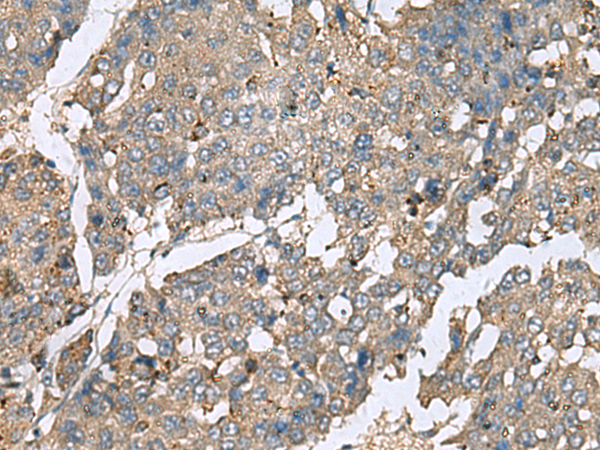

分类: 科研抗体货号: P10217别名: AXCAM; BIG-2应用: IHC反应种属: Human, Mouse, Rat